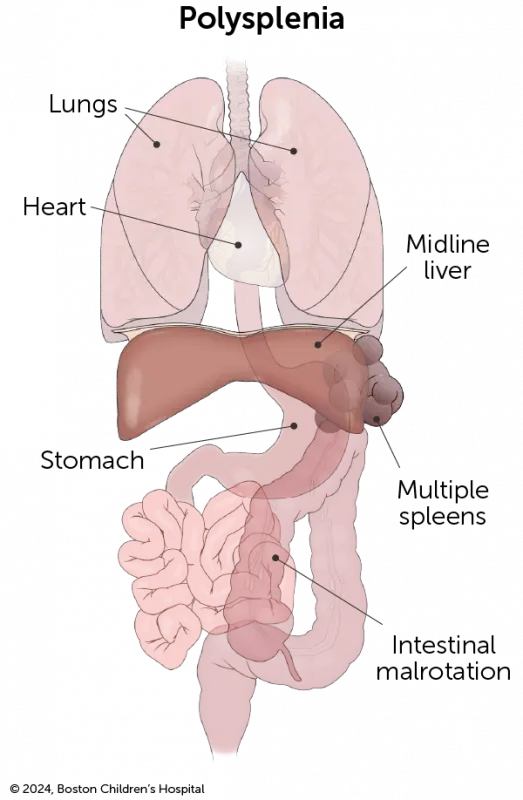

Check out our downloadable pamphlet for a summary about heterotaxy syndrome. It provides details about the diagnosis, testing, treatment at Boston Children’s, and more.